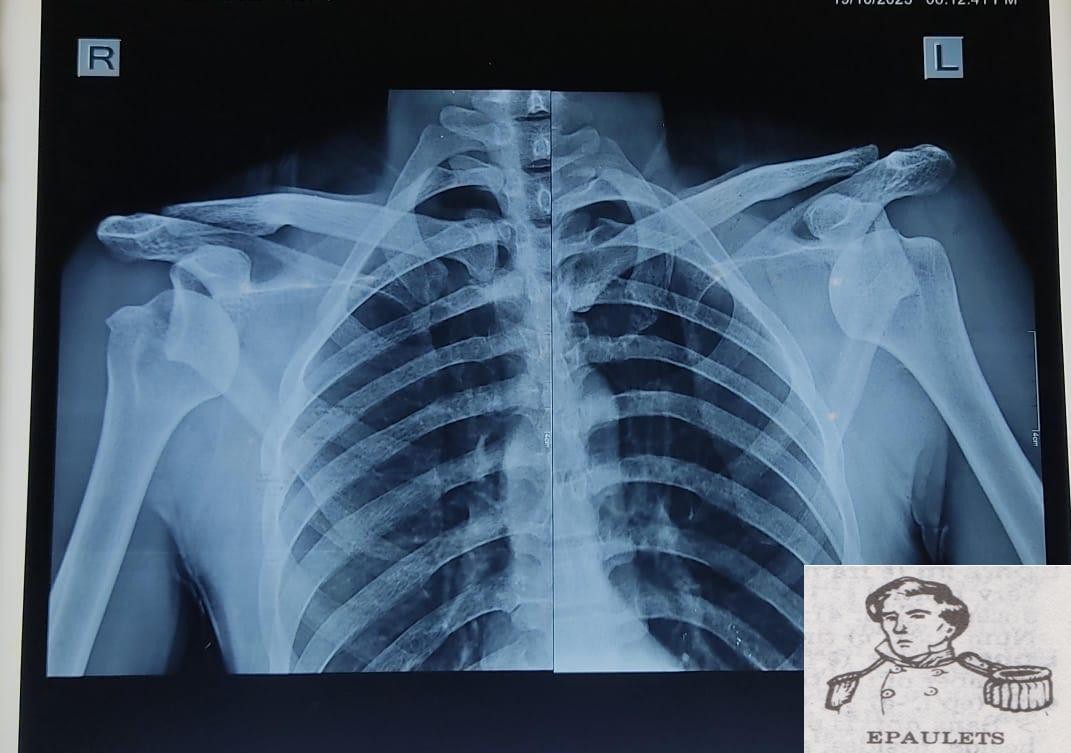

Radiographs (antero‑posterior views of both shoulders) confirmed bilateral anterior dislocations of the glenohumeral joints without associated fracture (Fig. 3).

Figure 3: Pre-reduction anteroposterior radiograph showing bilateral anterior dislocation of the humeral heads (right and left) projected anterior to the glenoid fossae with squaring of both shoulders (Epaulets Sign). There is no associated fracture.

The Light bulb sign was absent. Baseline blood investigations were normal and done to rule out hypoglycemia and dyselectrolytemia.